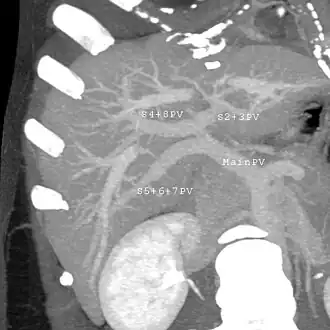

Couinaud classification system

In the widely used Couinaud system, the functional lobes are further divided into a total of eight subsegments based on a transverse plane through the bifurcation of the main portal vein.[30] The caudate lobe is a separate structure that receives blood flow from both the right- and left-sided vascular branches.[31][32] The Couinaud classification divides the liver into eight functionally independent liver segments. Each segment has its own vascular inflow, outflow and biliary drainage. In the centre of each segment are branches of the portal vein, hepatic artery, and bile duct. In the periphery of each segment is vascular outflow through the hepatic veins.[33] The classification system uses the vascular supply in the liver to separate the functional units (numbered I to VIII) with unit 1, the caudate lobe, receiving its supply from both the right and the left branches of the portal vein. It contains one or more hepatic veins which drain directly into the inferior vena cava.[30] The remainder of the units (II to VIII) are numbered in a clockwise fashion:[33]

With the recent advances of noninvasive imaging, living liver donors usually have to undergo imaging examinations for liver anatomy to decide if the anatomy is feasible for donation. The evaluation is usually performed by multidetector row computed tomography (MDCT) and magnetic resonance imaging (MRI). MDCT is good in vascular anatomy and volumetry. MRI is used for biliary tree anatomy. Donors with very unusual vascular anatomy, which makes them unsuitable for donation, could be screened out to avoid unnecessary operations.

MDCT image. Portal venous anatomy contraindicated for liver donation -